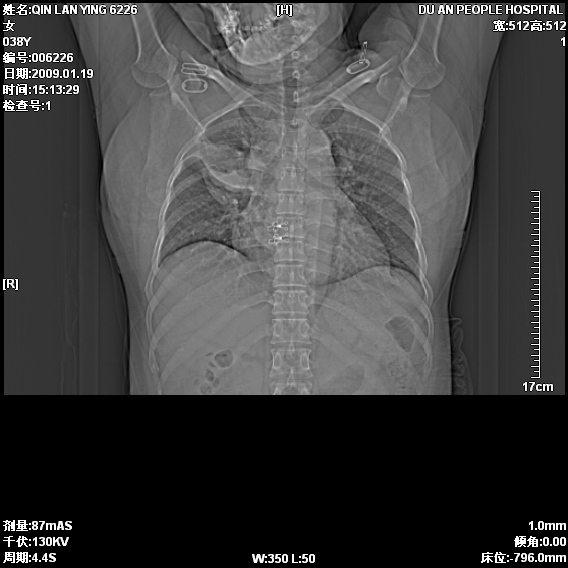

女,38岁,胸疼1个月。wbc:1万4

1)右肺中央型肺癌并右肺上叶阻塞性肺炎、节段性肺不张,纵隔淋巴结转移、右侧胸膜转移、肝脏转移。2)右侧胸腔少量积液。

1、右侧中央型肺癌并阻塞性肺不张,纵隔内、主动脉弓旁、右肺门淋巴结及肝脏转移可能性大,建议纤支镜进一步检查。

2、右侧胸腔积液。

本病例有几个容易诊断的地方:1、右肺上叶前段支气管闭塞,肺不张。2、淋巴结明显肿大。3、肝脏多个类圆形低密度影呈“牛眼征”改变,高度提示转移。